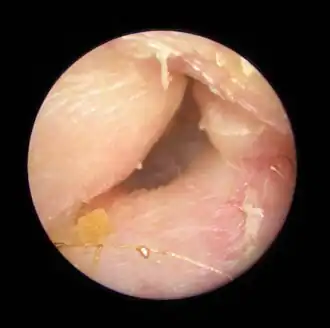

Description de cette image, également commentée ci-après

Exostoses dans le conduit auditif, vues par otoscopie.